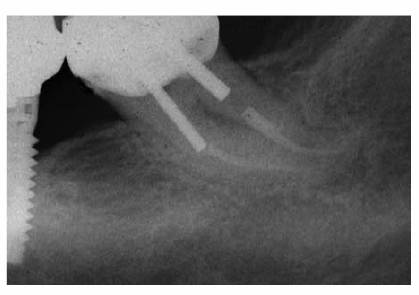

Figure 19-17D: A maxillary first molar with a periapical radiolucency.

Figure 19-17E: A gutta-percha point placed in the distal pocket. Pulp testing through an occlusal opening revealed a vital pulp. The cause of the radiolucency was of periodontal origin and therapy followed that course.